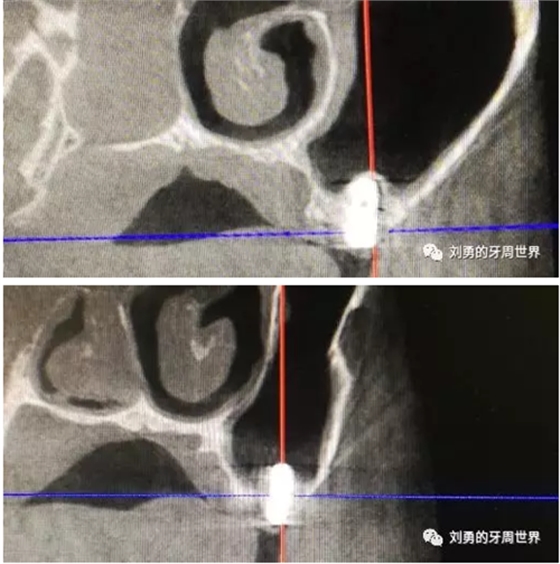

在手術(shù)之前行ct檢查如下圖:

可見B5種植體已經(jīng)脫落進入上頜竇,而上頜竇黏膜已經(jīng)出現(xiàn)明顯的炎癥,上頜竇黏膜明顯增厚,(在二期切開手術(shù)之前上頜竇黏膜厚度正常)。而在ct上可以看到左側(cè)上頜竇中鼻道開口不通暢。